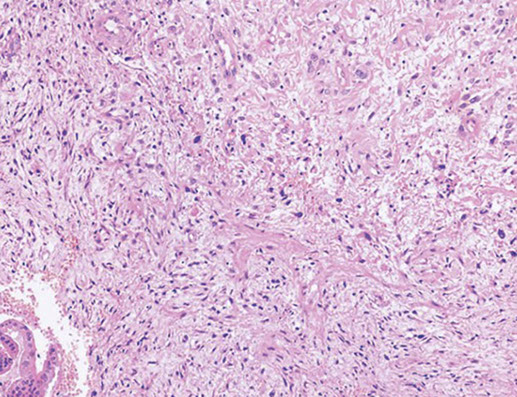

Malignant mixed mullerian tumor (MMMT, carcinosarcoma)

Micro: biphasic, c carcinoma and sarcomatous parts

Epithelial portion can be em, serous, clear cell, undifferentiated, squamous, while stroma can be homologous / heterologous

Homologous: (native to the tumor site) endometrial stromal sarcoma or leiomyosarcoma or undifferentiated sarcoma

Heterologous: (not native to the tumor site) muscle, cartilage, bone, fat

- common to see lymphangio invasion

IHC: (+) keratins (+ in carcinomatous and sarcomatous parts), EMA, p53, vimentin, fibronectin

Px: 1/3 alive at 5-years

MMMT

Carcinosarcoma